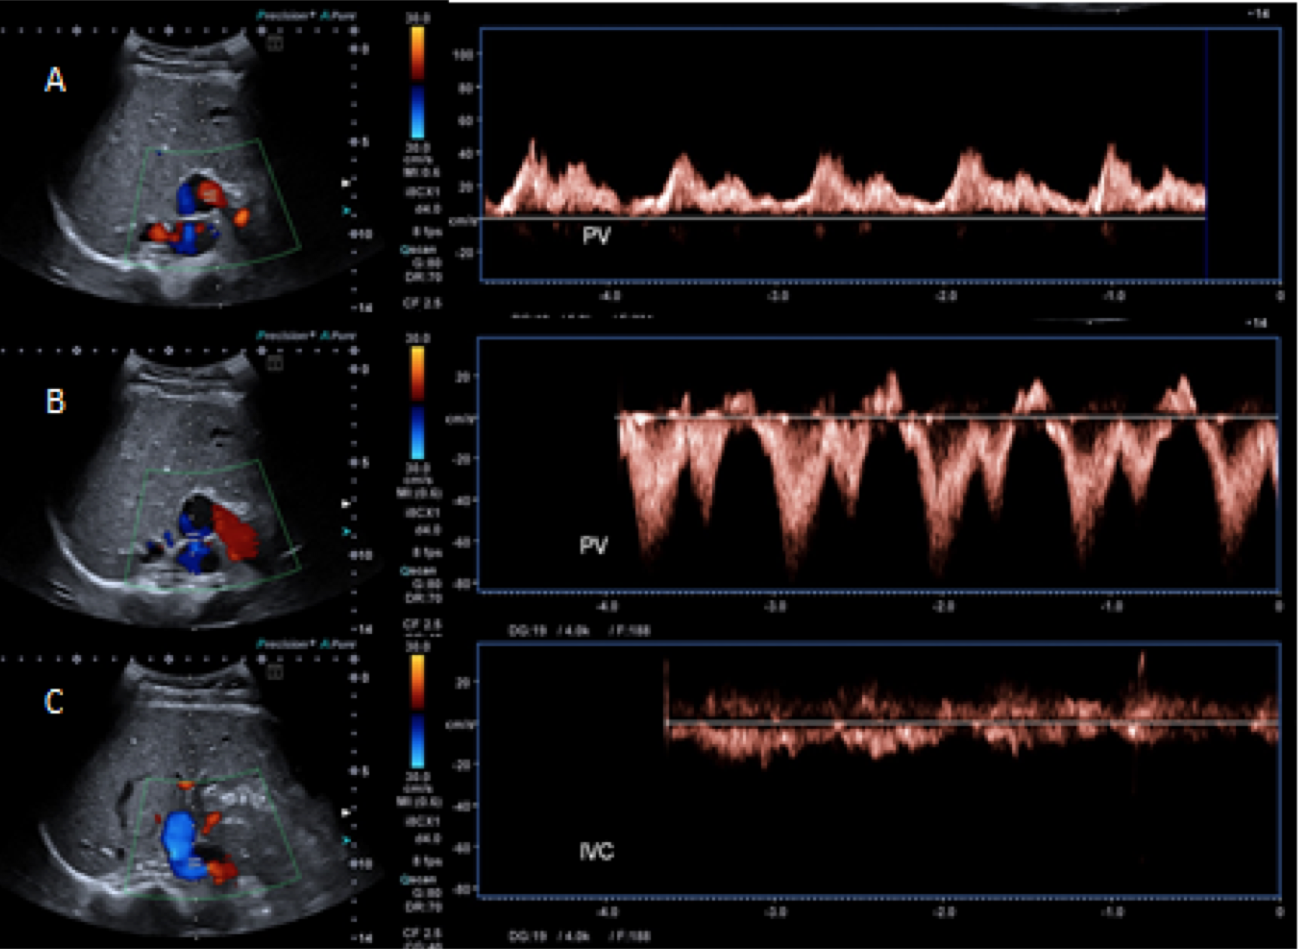

Figure 2B – Ultrasound video (see attachment) demonstrating right branch of the portal vein draining into the IVC

Based upon the MRI findings, she was investigated for any underlying causes of elevated manganese. On abdominal ultrasound, the liver had a normal size, outline, and echotexture. Interestingly, the right branch of the portal vein appeared to drain directly into the inferior vena cava. A congenital porto-systemic shunt was confirmed on a triple phase CT study of the liver which proved that the right branch of the portal vein drained directly into the IVC. There were no features to suggest chronic liver disease or collateralisation of the vessels.

3. Ultrasound studies play an important role in the diagnosis of porto-systemic shunts.